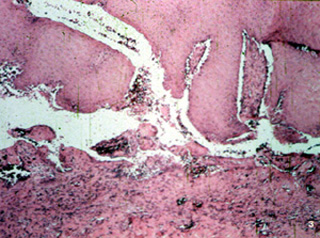

| Hay una apariencia característica histológica de la

enfermedad. Las vesículas son intraepiteliales generalmente suprabasal

. También hay una respuesta inflamatoria mixta en el tejido conjuntivo

subyacente. |